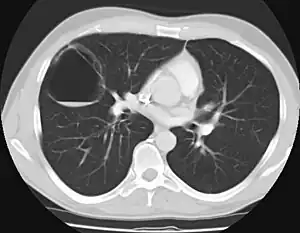

CPAM on chest radiograph in a newborn. Large cystic changes in the left lung, leading to a mediastinal shift to the right due to their mass effect.